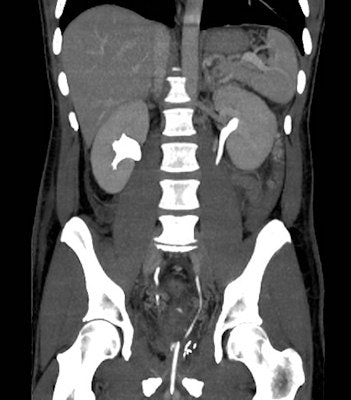

In urologic patients, a postoperative MDCT study should include a preliminary unenhanced acquisition to detect hyperattenuating blood and abnormal air collections, arterial and venous-phase images after intravenous contrast medium (CM) injection to assess the solid organs and identify extravascular CM indicating active bleeding, and excretory phase imaging. Images are obtained at least 5 minutes to 20 minutes (up to 1-2 hours) after CM, in order to demonstrate the opacified urinary cavities and detect iodinated urine leaks and urinomas, they wrote.

MDCT studies should be complemented with multiplanar reformations and 3D volume-rendered images to effectively depict the postoperative anatomy and salient findings. To limit the radiation dose during multiphasic acquisitions, the researchers have developed split-bolus MDCT urography protocols that allow for combined renal vascular, parenchymal, and excretory acquisition.

MDCT urography protocol should include preliminary unenhanced scans, an initial 30 mL CM bolus injected at 2 mL/s flow for urinary opacification, a seven minute delay, a second (50 ml at 1.5 mL/s), and third (65 mL at 3 mL/s) CM injection separated by 20 seconds to provide parenchymal and vascular visualization respectively, followed by a single MDCT volumetric acquisition.

When performed properly, triple-bolus MDCT urography can provide simultaneous renovascular, corticomedullary, nephrographic, and excretory imaging with a reduced effective radiation dose compared to the usual multiphasic MDCT protocols, they stated.